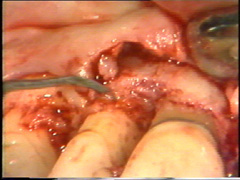

Las superficies de la raíz se limpian

(raspado y alisado radicular) cuidadosamente y el tejido de granulación en los

defectos óseos (cráter) es eliminado. En la superficie bucal del segundo premolar hay

un cráter óseo y cálculo en la supericies dental adyacente.

El cálculo del segundo premolar

está unido firmemente a la superficie dental y es un proceso tedioso el

quitarlo.

En la superficie

palatina del central, hay un defecto grande en la superficie de la raíz. Probablemente

sea una fractura que ocurrió en relación con el accidente. El tejido de

granulación se ha formado en el defecto que se limpia completamente. Postoperatoriamente es necesario poner

apicalmente el colgajo en relación con el defecto de la raíz para crear una condición higiénica manejable